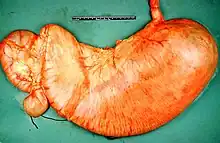

![]() | |